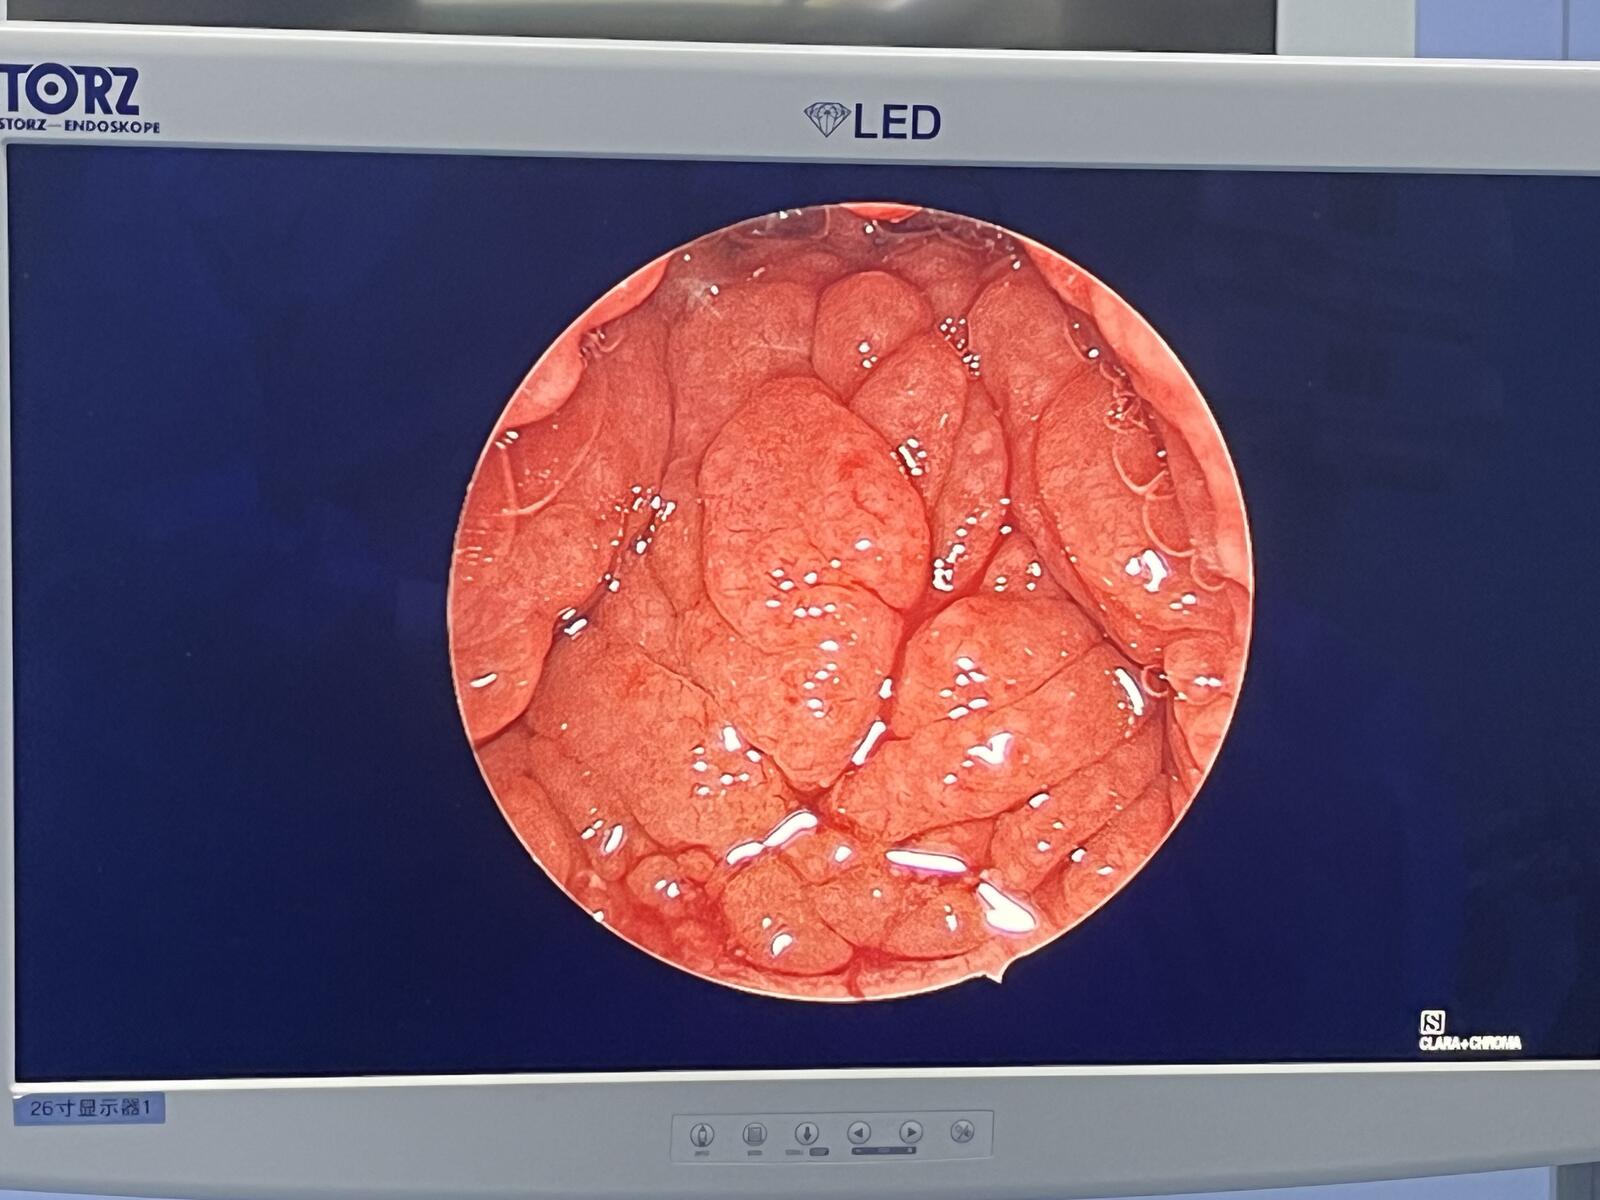

腺样体肥大

处理到位的软腭层面